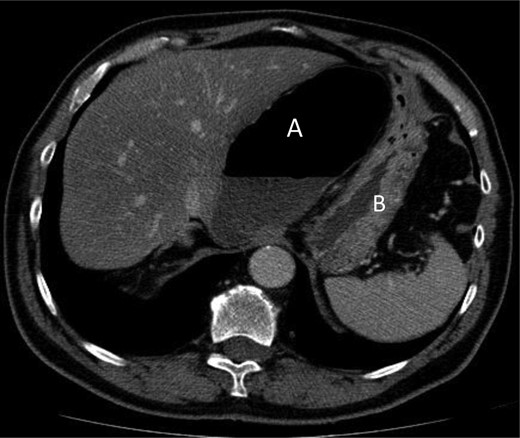

A 69-year-old patient presented to our emergency room with progressive dull abdominal pain and distension without nausea, vomiting or change in bowel habits. Physical examination showed pain with moderate guarding in the right upper and lower quadrants. A plain abdominal X-ray and a CT scan were performed. Radiological findings suggested the diagnosis of an internal hernia through the epiploic foramen and containing the right colon with important distension of the caecum (Fig. 1). Surgical exploration was then performed using an open approach. At laparotomy, we found an internal herniation of the caecum and the entire ascending colon through the foramen of Winslow (Figs 2 and 3). After hernia reduction, multiple patchy areas of caecal necrosis were observed (Fig. 4). A formal right hemi-colectomy was therefore performed. The postoperative recovery was uneventful.

Axial section through upper abdomen showing distended caecum with air-fluid level (A) with the displacement of the stomach (B) laterally.